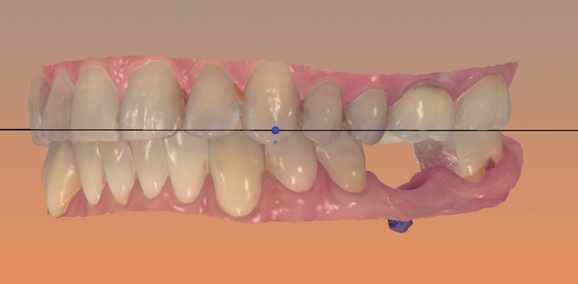

Fig 16. Presurgical design and fabrication of restorative components based on virtual implant position, allowing for possible minor angle/linear deviations (Fig 16 through Fig 18). Component options are broad and may include a custom healing abutment and bondable polymethyl methacrylate restoration; a single restoration with an engaging or non-engaging base; provisional fixed partial dentures (Fig 19), which can be indexed intraorally to prepared temporary abutments; or a full-arch restoration to be indexed intraorally to prepared temporary abutments.

Figure 16

Fig 17. Presurgical design and fabrication of restorative components based on virtual implant position, allowing for possible minor angle/linear deviations (Fig 16 through Fig 18). Component options are broad and may include a custom healing abutment and bondable polymethyl methacrylate restoration; a single restoration with an engaging or non-engaging base; provisional fixed partial dentures (Fig 19), which can be indexed intraorally to prepared temporary abutments; or a full-arch restoration to be indexed intraorally to prepared temporary abutments.

Figure 17

Fig 18. Presurgical design and fabrication of restorative components based on virtual implant position, allowing for possible minor angle/linear deviations (Fig 16 through Fig 18). Component options are broad and may include a custom healing abutment and bondable polymethyl methacrylate restoration; a single restoration with an engaging or non-engaging base; provisional fixed partial dentures (Fig 19), which can be indexed intraorally to prepared temporary abutments; or a full-arch restoration to be indexed intraorally to prepared temporary abutments.

Figure 18

Fig 19. Presurgical design and fabrication of restorative components based on virtual implant position, allowing for possible minor angle/linear deviations (Fig 16 through Fig 18). Component options are broad and may include a custom healing abutment and bondable polymethyl methacrylate restoration; a single restoration with an engaging or non-engaging base; provisional fixed partial dentures (Fig 19), which can be indexed intraorally to prepared temporary abutments; or a full-arch restoration to be indexed intraorally to prepared temporary abutments.

Figure 19